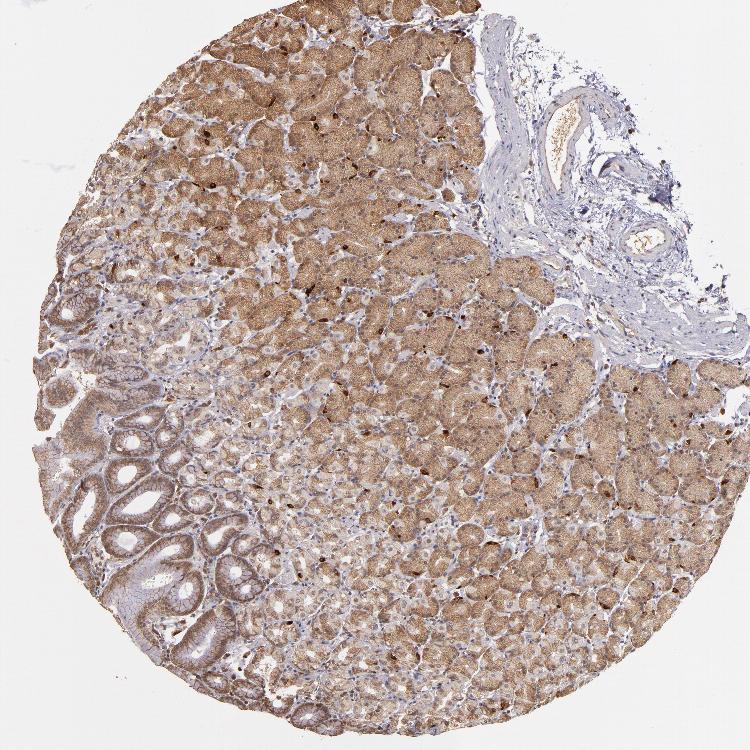

TISSUE PRIMARY DATA STOMACH Show tissue menu

STOMACH 1 - Antibody stainingi

Antibody staining in the annotated cell types in the current human tissue is reported as not detected, low, medium, or high, based on conventional immunohistochemistry profiling in selected tissues. This score is based on the combination of the staining intensity and fraction of stained cells.

Each image is clickable and will lead to virtual microscopy that enables deeper exploration of all samples and also displays staining intensity scores, fraction scores and subcellular localization as well as patient and tissue information for each sample.

Antibody HPA001620Antibody HPA024184

Glandular cells HighHigh